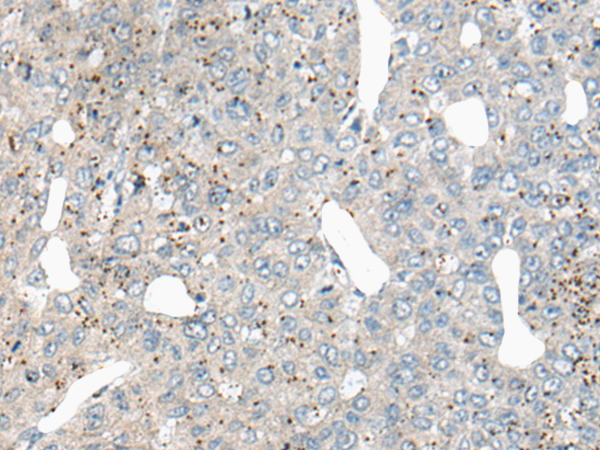

分类: 科研抗体货号: P13182别名: CIAB1; TAOS1; ORAOV1应用: IHC反应种属: Human